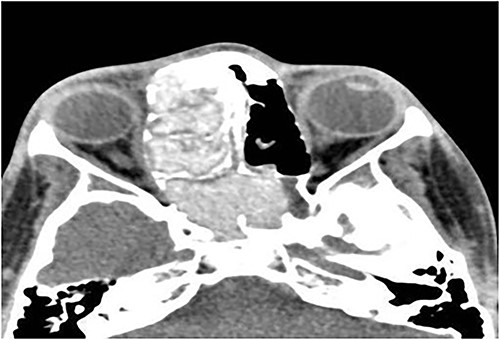

A 13-year-old male presented with progressive right-sided nasal obstruction followed by slowly progressive right eye proptosis noticed by parents for 1 year duration. CT scan of the paranasal sinuses (Fig. 2) confirmed the diagnosis of AFS. The child underwent FESS and received medical treatments post-operatively. The patient remained symptom-free for 4 years follow-up.

Axial CT paranasal sinuses shows the right ethmoid and sphenoid sinuses with complete obliteration and hyperdense (metallic) contents. It is associated with expansion of the ethmoid sinuses and lateral displacement of the right lamina papyracea causing right eye proptosis.